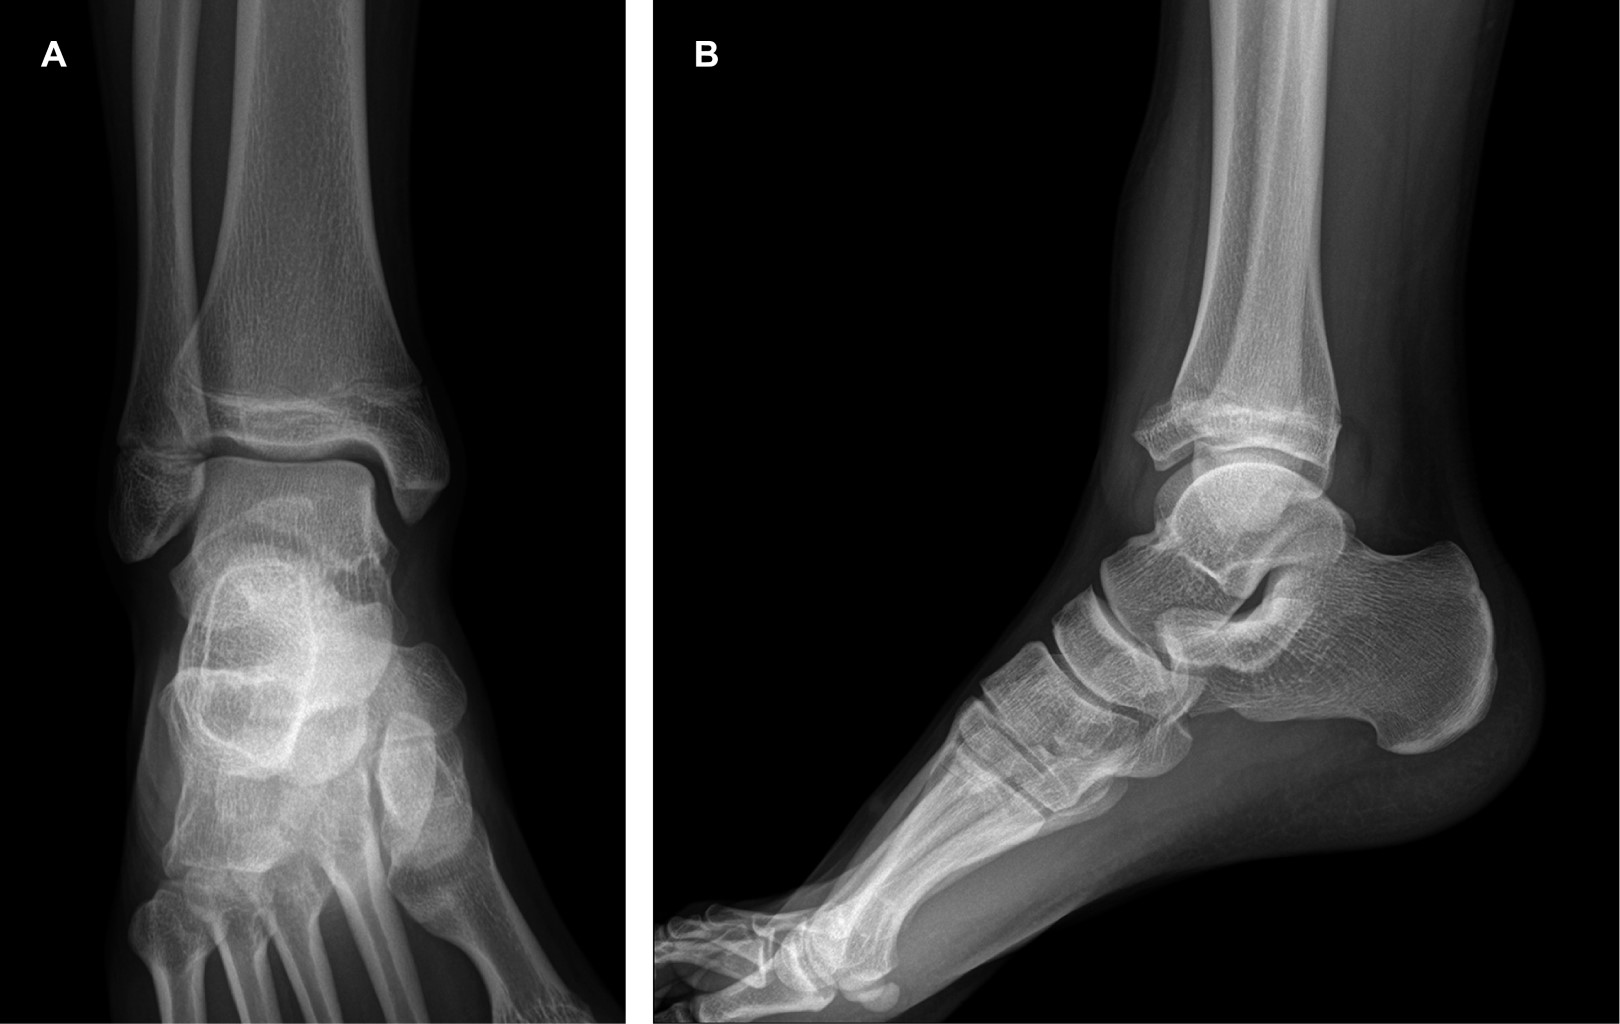

A las 10 semanas el paciente presenta marcha con apoyo total. Se establece evolución satisfactoria en el seguimiento según las escalas de Foot and Ankle Ability Measures de 97%, escala visual análoga de dolor de 0/10, AOFAS de 100 y SF-36 de 98.00 (Figura 2A y B).

Figura 2